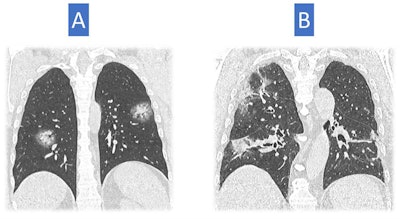

Italy was quite hard hit, said Dr. Nicola Sverzellati, head of the radiology unit at the University Hospital of Parma. The country's first patient, a 38-year-old man, presented at an emergency department in Codogno in February with acute respiratory distress syndrome. Only a few weeks later, the government locked Codogno and neighboring villages down. As the virus spread through the country, clinicians across Italy began tracking chest CT features of COVID-19, including ground-glass opacities, multilobe involvement, bilateral distribution, and posterior involvement.